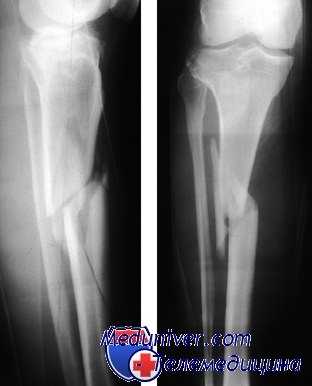

(Слева) При рентгенографии в передне-задней проекции определяется поперечный перелом в сочленения средней и дистальной трети диафиза большеберцовой кости с 50% боковым смещением. У перелома малоберцовой кости отмечается полное медиальное смещение. Поперечные переломы отражают больше энергии чем спиральные.

(Справа) При рентгенографии в боковой проекции у этого же пациента определяется почти полное переднее смещение перелома большеберцовой кости. Переломы в этой локализации обладают большей вероятностью несращения. (Слева) При рентгенографии в передне-задней проекции определяется четкий и явный перелом в области сочленения средней и дистальной трети диафиза бедренной в и перелом средней части малоберцовой костей. Перелом проксимального диафиза большеберцовой кости труднее отличить.